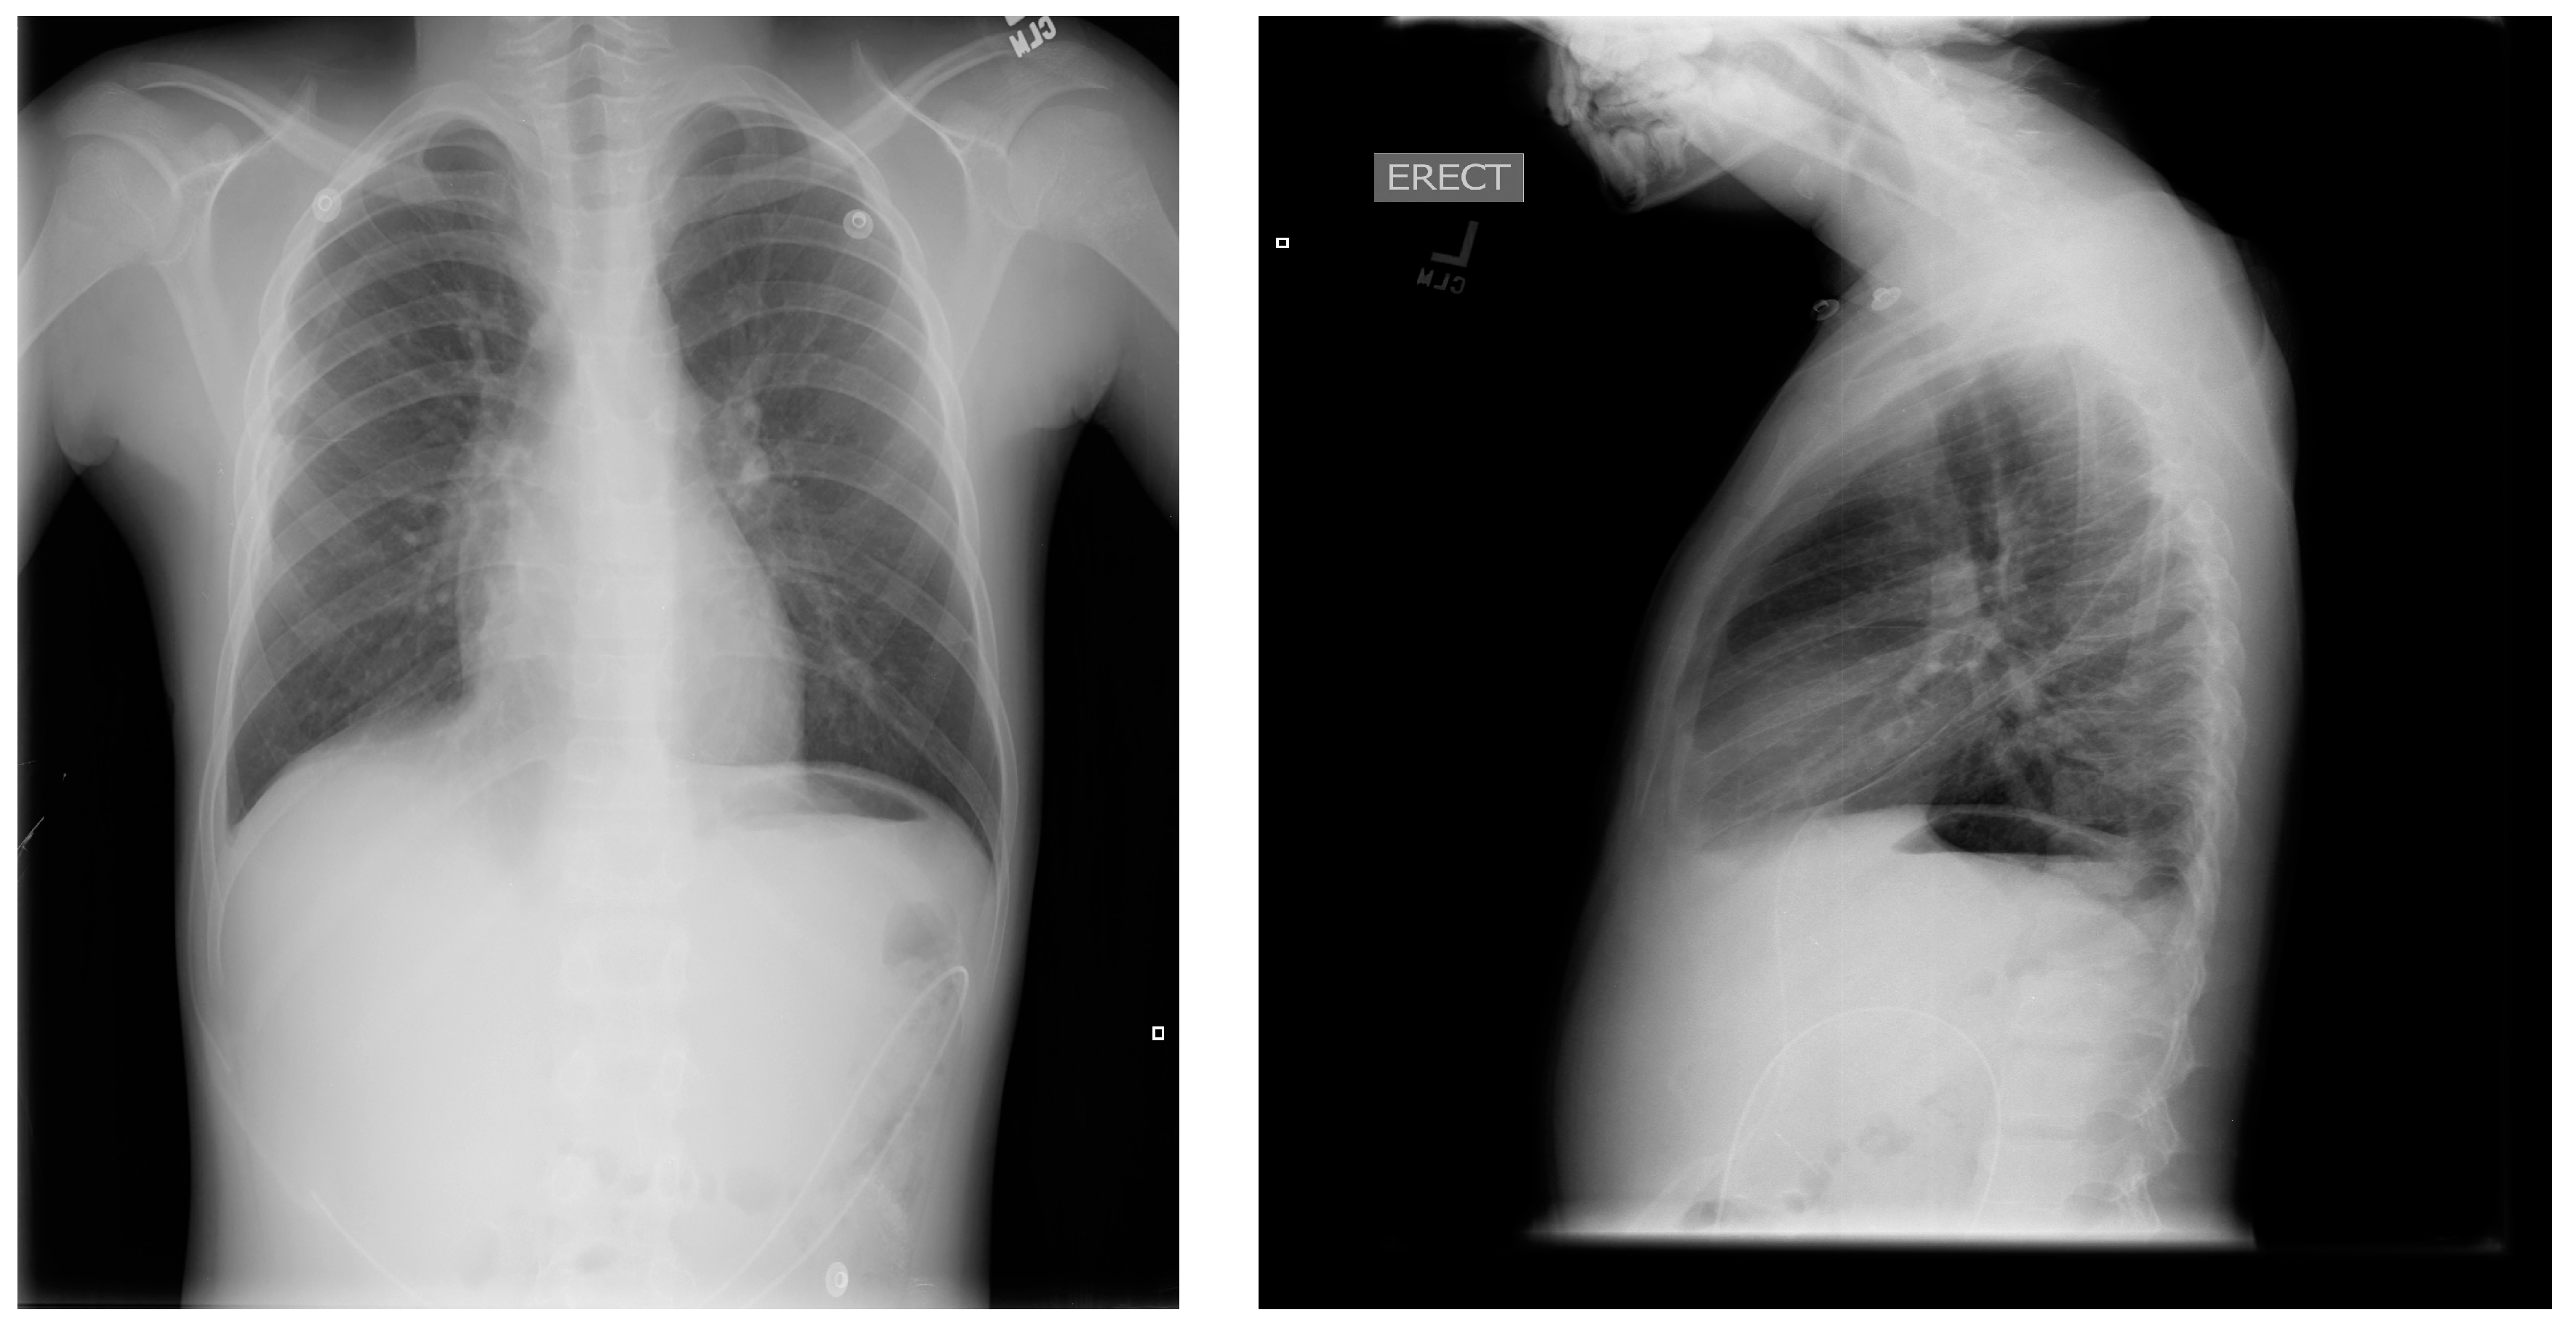

Figure 6.

Post-operative chest X-rays, showing reversed pleuroperitoneal shunt in right chest and abdomen.